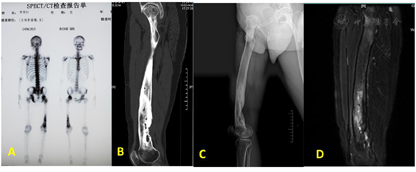

X线检查提示:右股骨中下段骨髓炎;CT检查提示:右侧股骨可见死骨形成;磁共振检查提示:右股骨中下段高水肿信号改变,结合病史考虑感染;全身骨显像(核素扫描)提示:右侧股骨中下段代谢性活跃,符合骨髓炎表现(见图2)。血常规检查:白细胞6.28*109/L,中性粒细胞61.44%,血沉57mm/h,C反应蛋白62.8mg/L,降钙素原0.093ng/ml。

患者长期流脓病史,进行过多次开窗手术治疗,术后伤口未完全愈合,形成窦道,患肢出现功能障碍,CT检查可见死骨形成,全身核素扫描提示右侧股骨中下段代谢性活跃,符合骨髓炎表现,根据以上资料患者明确诊断为:1.右股骨骨髓炎(Cierny-Mader Ⅳ型BL型),2.右髋膝关节僵硬。